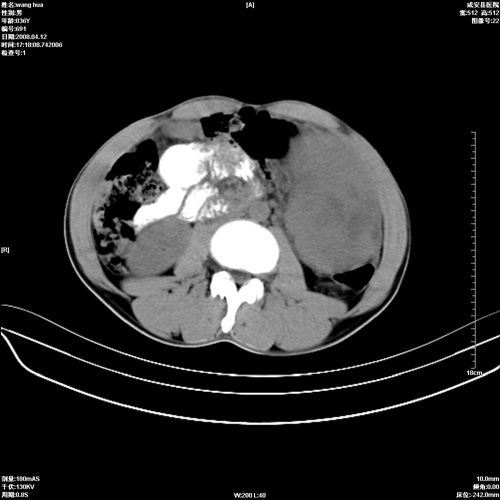

标题: CT12809:男36岁,自感上腹胀5天,B超诊断为脾肾之间占位,血 [打印本页]

标题: CT12809:男36岁,自感上腹胀5天,B超诊断为脾肾之间占位,血

请各位老师先分析一下定位 明天做增强

脾脏病变,密度不均,可见钙化,考虑脾血管瘤,建议增强

脾脏明显增大,其内见巨大低密度灶,境界不清,病史较短,考虑恶性病变脾血管内皮细胞肉瘤可能。建议增强扫描与脾脏淋巴瘤及血管瘤鉴别。